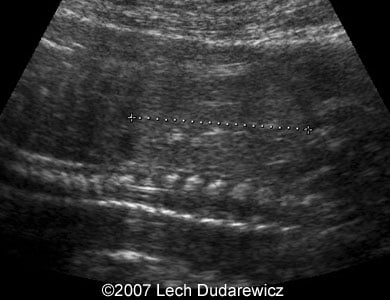

Here are some second trimester ultrasound images of anhydramnios caused by autosomal recessive polycystic kidney disease.

Images 3, 4: Parasagittal planes through the fetal kidneys with echogenic parenchyma.